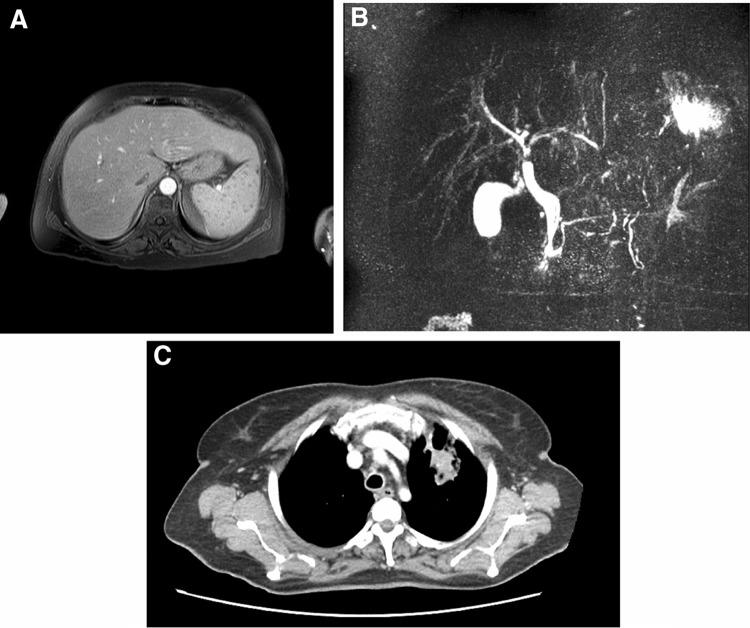

Sarcoidosis is a systemic disease characterized by an immune-mediated disorder, which leads to the development of non-caseating granulomas in the involved organs. More than 90% of patients with sarcoidosis present lungs and lymphatic system involvement at onset, while less than 10% has an isolated extrapulmonary localization. Here, we describe the case of an elderly patient with isolated hepato-splenic onset (multiple splenic lesions at imaging and cholestasis), and subsequent pulmonary involvement. The liver biopsy showed the presence of non-caseating granulomas, suggesting sarcoidosis. Despite the complete recovery was obtained with steroid therapy, after dosage reduction the patient presented watery diarrhea. Endoscopic investigations with biopsies were performed, describing the presence of an important lympho-plasmacytic infiltrate of terminal ileum mucosa with typical aspects of inflammatory bowel disease. The symptomatology completely disappeared after steroid dosage increase. This case confirms that sarcoidosis could present in a very atypical way, involving several organs in a different manner at the same time and that every symptom should not be underestimated, despite the rare presentation.

结节病是一种以免疫介导的疾病为特征的全身性疾病,可导致受累器官出现非干酪样肉芽肿。超过90%的结节病患者在发病时出现肺部和淋巴系统受累,而不到10%的患者仅有肺外孤立性病变。在此,我们描述了一例老年患者,以孤立性肝脾起病(影像学检查发现多个脾脏病变及胆汁淤积),随后出现肺部受累。肝脏活检显示存在非干酪样肉芽肿,提示结节病。尽管使用类固醇治疗后完全康复,但在减量后患者出现水样腹泻。进行了内镜检查及活检,描述了末端回肠黏膜存在重要的淋巴细胞和浆细胞浸润,具有炎症性肠病的典型表现。增加类固醇剂量后症状完全消失。该病例证实结节病可能以非常不典型的方式出现,同时以不同方式累及多个器官,并且尽管表现罕见,但每个症状都不应被低估。